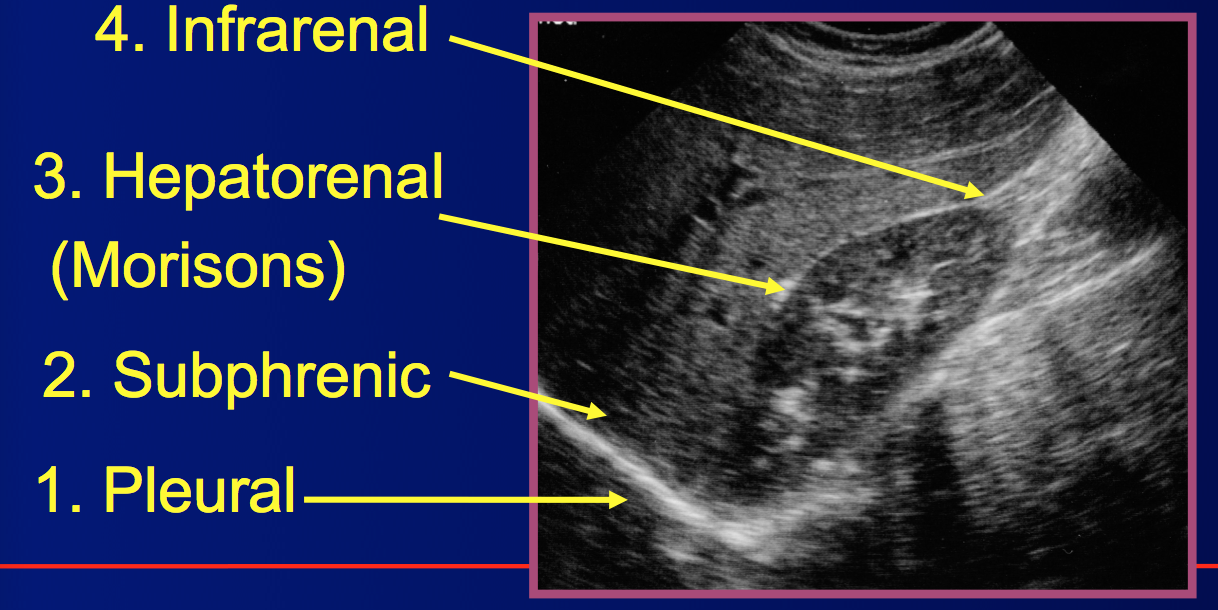

Where is this.

Label it/

RUQ

Other name for hepatorenal space:

Morison’s